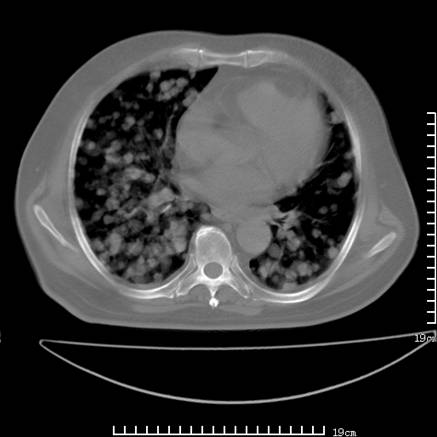

张男,75岁,干咳半年余,小便不利二年,b超检查前列腺增大,未见明显肿块;前列腺癌血生化检查多项指标明显增高。

双肺内多发转移瘤,纵膈淋巴结转移。来源前列腺?建议盆腔mri进一步检查。

双肺转移满了。

两肺广泛转移瘤。